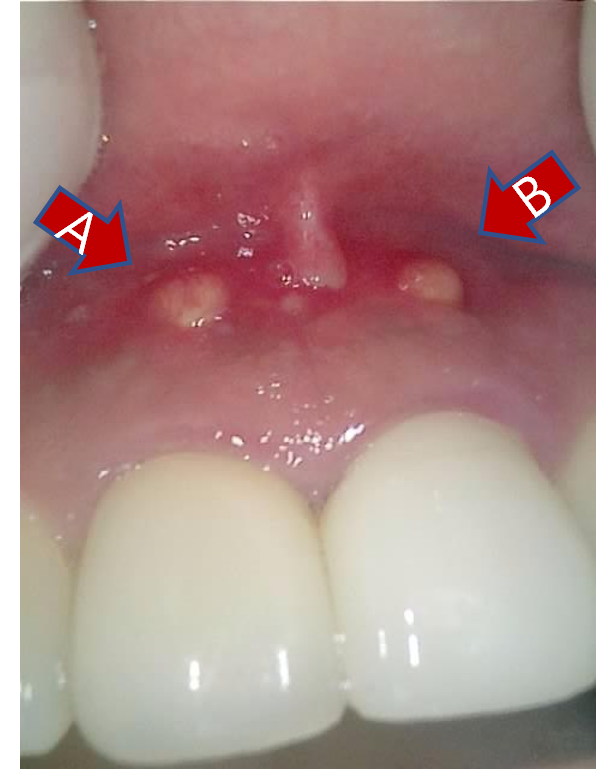

말씀하신 부위를 보니, 앞니 잇몸에 난 뾰루지, 고름주머니 혹은 누공이 2개나 보인다.

앞니 잇몸에 뾰루지가 2개 생겼는데, 신경치료를 해도 안 없어짐

눌렀을 때 말랑해서, 뼈 같지는 않았다.